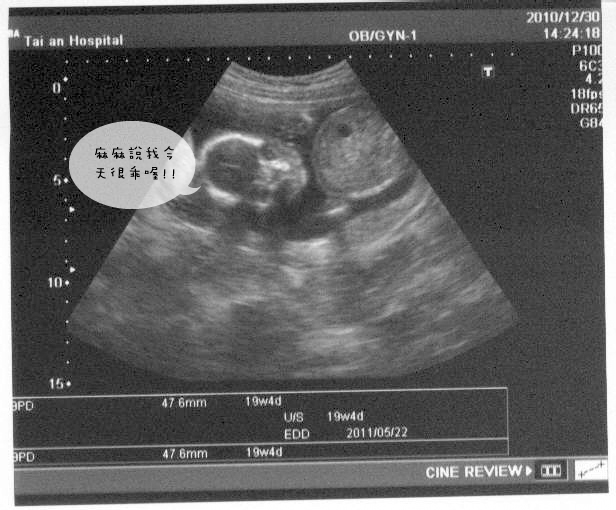

今天不是例行的產檢,是回去看上次做的檢查報告~肌肉萎縮症和母血唐氏症

安全過關~bingo

楚醫師順便檢查了小妞妞的臉,確定沒有兔唇,一切正常~

這張照片很清楚的看見小妞妞的五官,還有看起來像是在跟我們say hi的小手掌

好可愛阿~